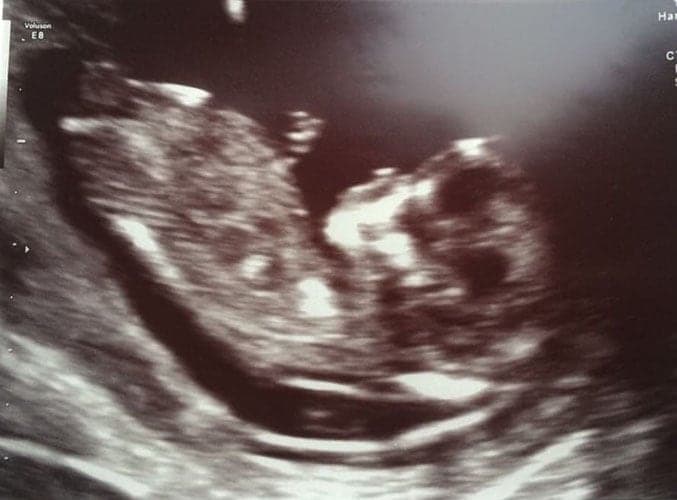

Ultraschallbilder aus dem 3. Trimester (29. bis 40. SSW)

Im dritten Trimester der Schwangerschaft ist das Baby so groß, dass es nicht mehr komplett auf ein Ultraschallbild passt. Nun kann man wunderbare 3D-Ultraschalle des Gesichts machen. In diesem Semester nehmen die Babys nochmal rasant zu und wer Glück hat, kann auf seinem Ultraschall schon erste Gesichtszüge erkennen.